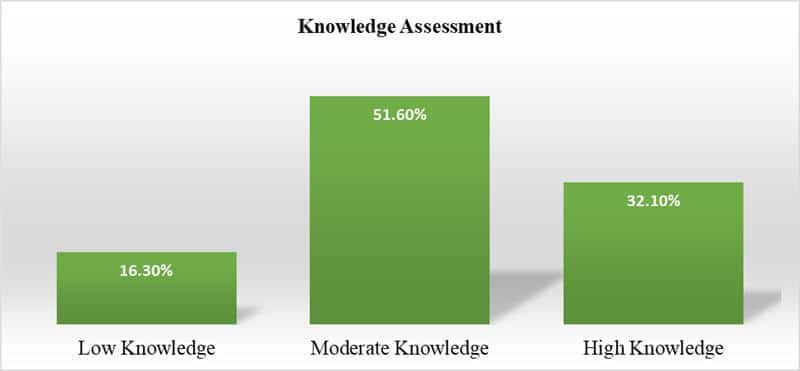

Knowledge and Practices of the Nurses Regarding Central Line Associated Infection at Tertiary Care Hospital, Peshawar, Pakistan

Background: Central Line-Associated Bloodstream Infections (CLABSIs) are a considerable source of increased mortality and morbidity during intensive care unit stays....Read More